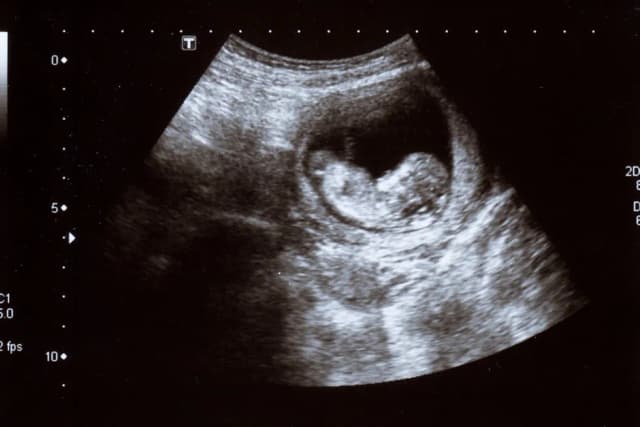

Kiedy słychać bicie serca dziecka? Sprawdź, co musisz wiedzieć

Dowiedz się, kiedy słychać bicie serca dziecka. Poznaj metody wykrywania tętna, rozwój płodu w ciąży oraz pierwsze objawy ciąży.